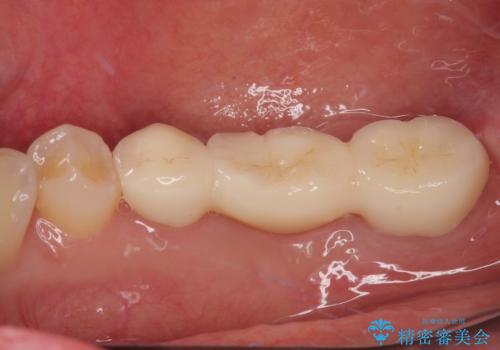

破折して抜歯が必要となった奥歯 オールセラミックブリッジ治療

再度の歯を根管治療したため、抜歯した部位の補綴治療は、強度の問題からブリッジよりもインプラントをおすすめしましたが、患者様希望によりブリッジを選択しました。

根管治療を行った奥歯をブリッジの支台歯としているため、咬合力による負担を軽減するために、就寝時にマウスピースを装着するように指導しています。